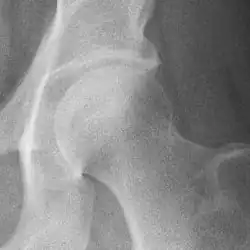

Osteoarthritis of the hip joint may also be graded by Tönnis classification. There is no consensus whether it is more or less reliable than the Kellgren-Lawrence system.[8]

Severe (Tönnis grade 3) osteoarthritis of the hip.

Tönnis classification[9]